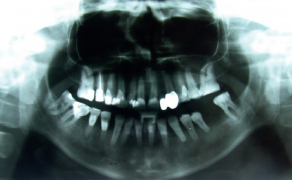

Agenezja drugich zębów przedtrzonowych stanowi jedną z najczęściej występujących wad rozwojowych uzębienia i jest istotnym problemem diagnostycznym oraz terapeutycznym w praktyce stomatologicznej. Prawidłowe rozpoznanie tej anomalii bywa utrudnione, szczególnie u pacjentów w wieku rozwojowym, dlatego wymaga kompleksowej oceny, wykraczającej poza analizę samego wieku chronologicznego. Kluczowe znaczenie ma uwzględnienie stopnia rozwoju zębów sąsiednich, z którymi rozwój drugich zębów przedtrzonowych pozostaje w [...]